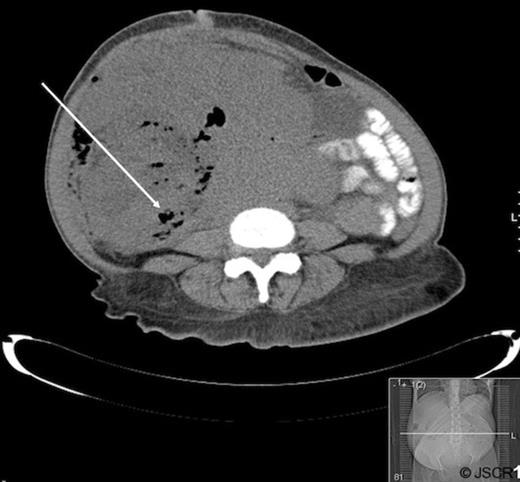

Patient A is a 67 year old female with a history of pelvic leiomyosarcoma and total abdominal hysterectomy with bilateral salpingo-oopherectomy who presented with abdominal discomfort, early satiety and weight loss. On physical exam she was noted to have a large, firm abdominal mass. Admission labs revealed a marked leukocytosis (WBC=45 700) and blood cultures positive for E. coli. CT of the abdomen and pelvis revealed a mass occupying the pelvis and majority of the abdomen with air pockets, questionable portal venous gas and mild left hydronephrosis (Figure 1).

Abdominal and pelvic CT of patient A demonstrating a large mass with air pockets (arrow).